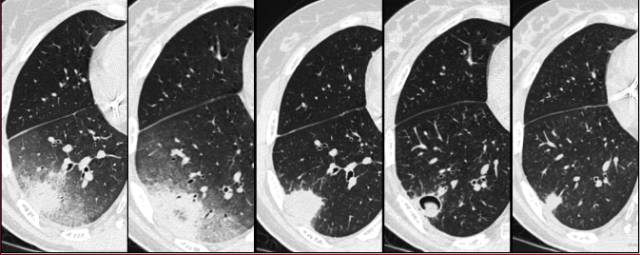

图1 一例酗酒和营养不良患者右肺慢性实变的进展。